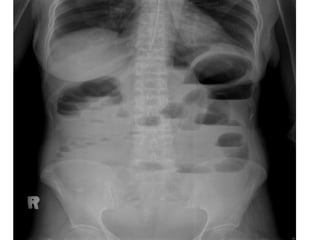

Radiology

• X – ray abdomen Erect

Air fluid levels

• X – ray abdomen Supine

Distended bowel

Small bowel

• Central and transverse lie

• Jejunum – Valvulae conniventes

(concertina / Stack of coins)

• Ileum – Characterless

• Colon – Haustral folds